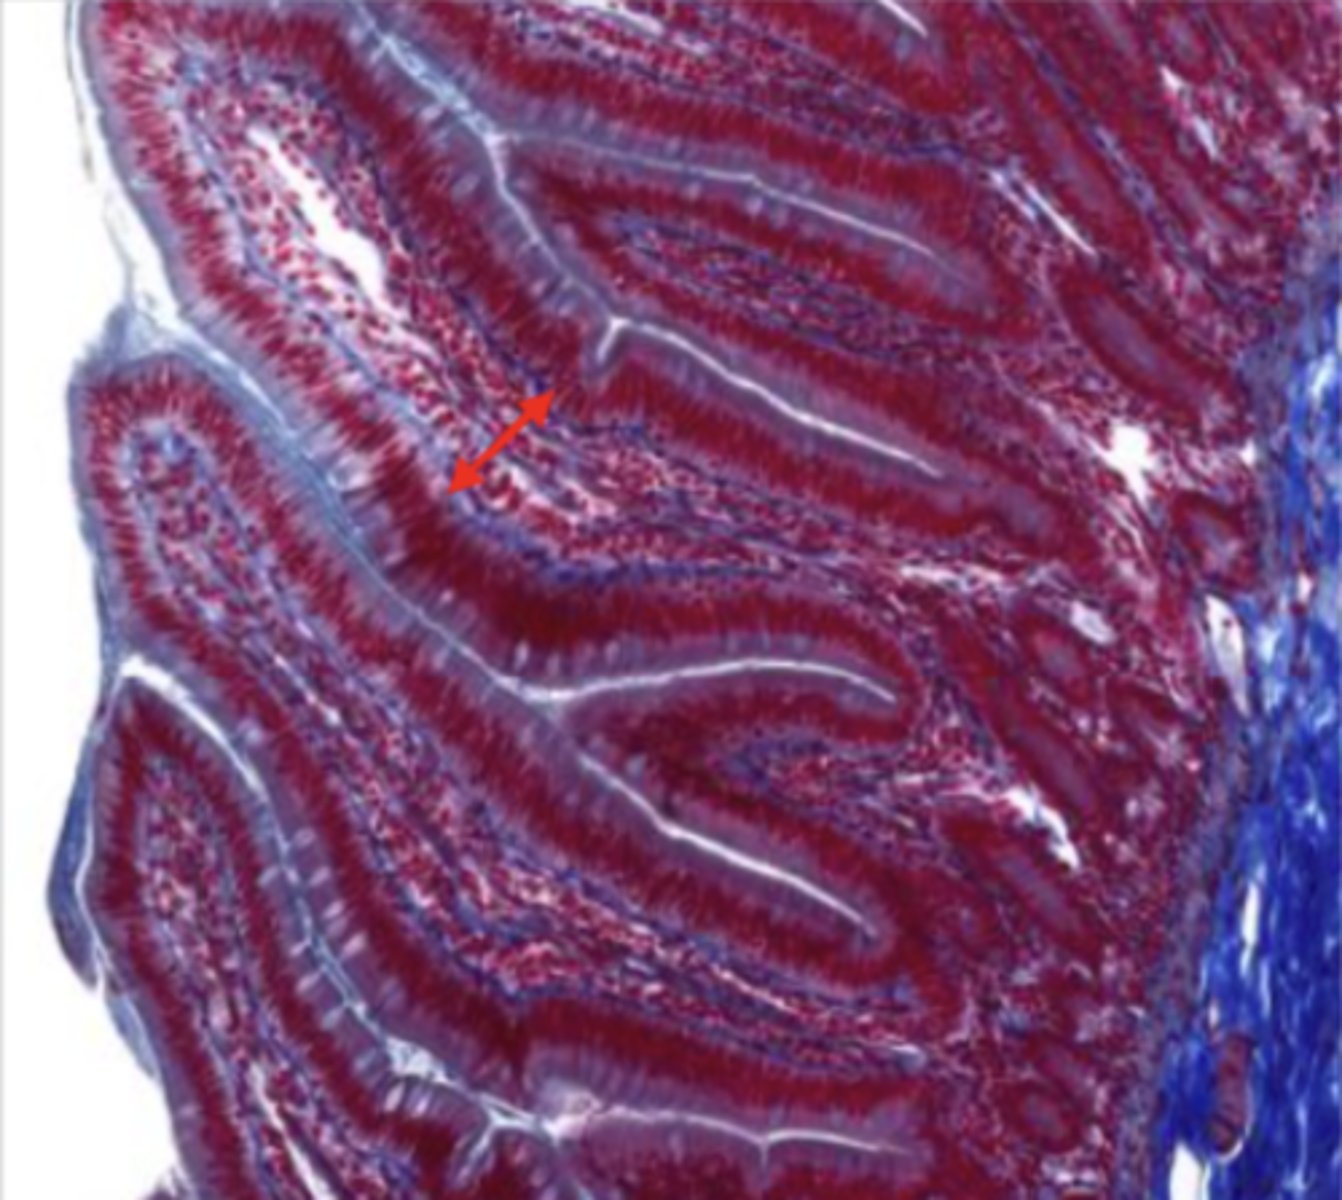

mucosa (esophagus)

mucosal epithelium (esophagus)

stratified squamous epithelium

lamina propria (esophagus)

muscularis mucosa (esophagus)

submucosa (esophagus)

contains glands and blood supply

muscularis externa (esophagus)

serosa/adventitia (esophagus)